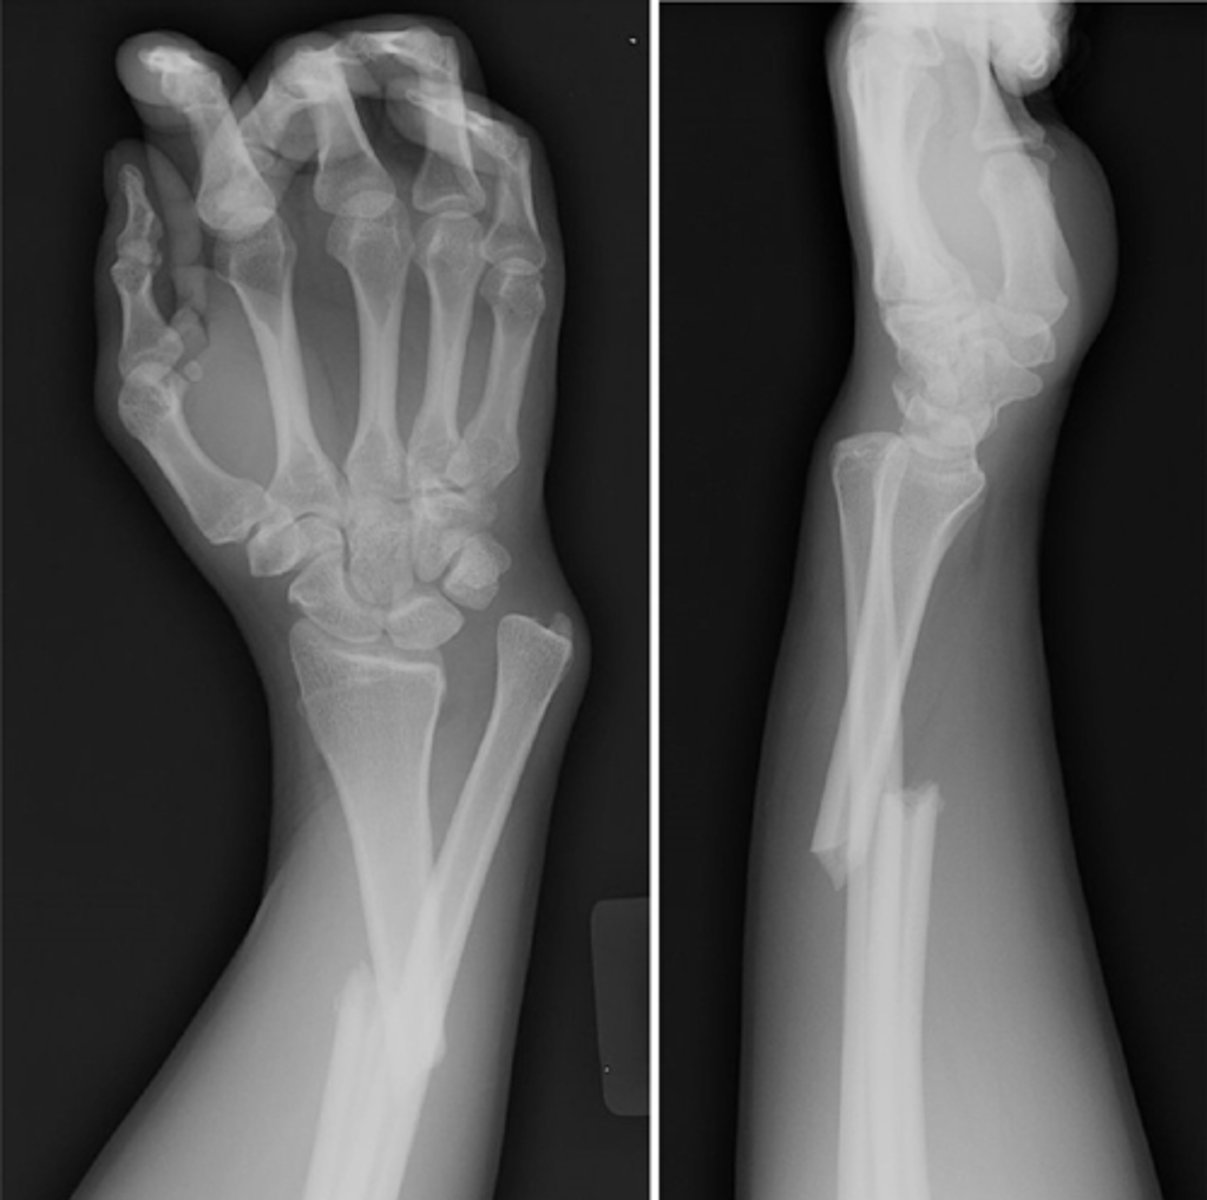

What does good position, good alignment look like vs. displaced with deviated alignment?

See image.

Name displacement based on the ________ fracture end in anatomical position

DISTAL!! -- i.e., "displaced medial, posterior, and overriding"

Name deviation based on the ________ bone angle in the ________ direction

DISTAL!! -- i.e., "deviated medial and anterior"